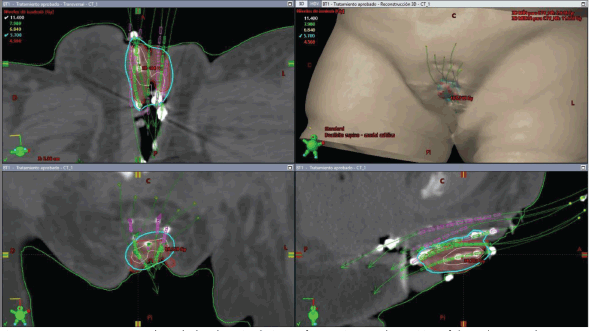

The initial plan suggested possible undercoverage in superficial regions of the tumour (Figure 3). Therefore, a custom silicone bolus containing four additional catheters was placed on the vulvar surface to enhance coverage of peripheral edges. A repeat CT confirmed improved D100 and D90 of the GTV while maintaining urethral dose constraints (Table 1, Figure 4).

Figure 4. Case 1. 3D treatment plan with bolus. The position of the catheters and the dosimetric distribution in the axial, coronal and sagittal planes are observed. On the left, fraction #2 to #5. On the right, fraction #6 to #8. In light blue, the isodose of 5.7 Gy; in white, the isodose of 11.4 Gy.